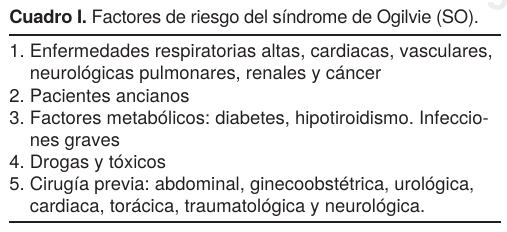

El síndrome de Ogilvie (SO) o pseudoobstrucción aguda del colon fue descrito en 1948 y publicado en la British Medical Journal por el doctor chileno William Heneage Ogilvie, nacido en Valparaíso el 14 de julio de 1887. Antes de Ogilvie, en 1896 Murphy4 describió por primera vez esta entidad durante una laparotomía, cuando encontró una distensión del colon proximal secundaria que él consideró un «espasmo del intestino». Había postulado que (como lo haría Ogilvie 50 años más tarde) el síndrome se caracterizaba por una dilatación masiva y aguda del colon, especialmente del lado derecho; varios reportes en la literatura señalan que afecta hasta el ángulo esplénico.3,4 Es una entidad clínica rara, predomina en pacientes del sexo masculino, generalmente se presenta en enfermos hospitalizados con alguna patología médica o quirúrgica grave y un porcentaje bajo en pacientes ginecoobstétricas2,3 (Cuadro I).

Los médicos de Urgencia, Medicina Interna y Ginecoobstetricia deben tener en mente esta patología y estar al tanto de su aparición, ya que si no se trata al inicio del cuadro clínico confirmado con estudios de laboratorio y gabinete, puede complicarse con perforación, peritonitis y muerte. Los índices de morbilidad varían en la literatura: entre más temprano se inicie el tratamiento, el porcentaje de curación es mayor hasta un 80%, si se emplean las medidas generales para este padecimiento, un esquema de fármacos procinéticos (Cuadro II) de la pasada y nueva generación,10 (mesaprida, itoprida, cinetaprida, etc.) y antibióticos según los resultados del laboratorio, por ejemplo eritromicina más neostigmina como control. Aún así, presentan un porcentaje de recidiva del 6-14%, de éstos sólo 20% llegan a ser quirúrgicos y son aquellos que recidivaron y/o llegaron con diagnóstico tardío o sin respuesta al tratamiento médico agresivo e intensivo de la descompresión con aplicación de sondas nasogástrica y rectal, corrección del desequilibrio hidroelectrolítico, control de cualquier anormalidad metabólica de fondo y descompresión endoscópica que por sus resultados buenos a excelentes (66-90%) compiten favorablemente contra una cirugía mayor, con mortalidad del (25 al 50%) y morbilidad del (3%).